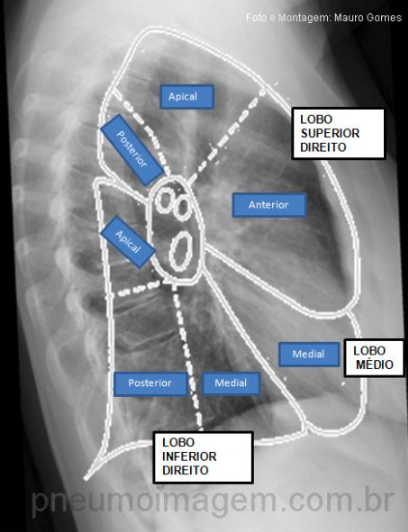

Localização de lobo médio e inferior de pulmão D e como diferenciar no Rx perfil

A

Lobo médio: anterior

Lobo inferior: posterior

Rx: se coluna vertebral está escondida por uma consolidação = lobo inferior atingido